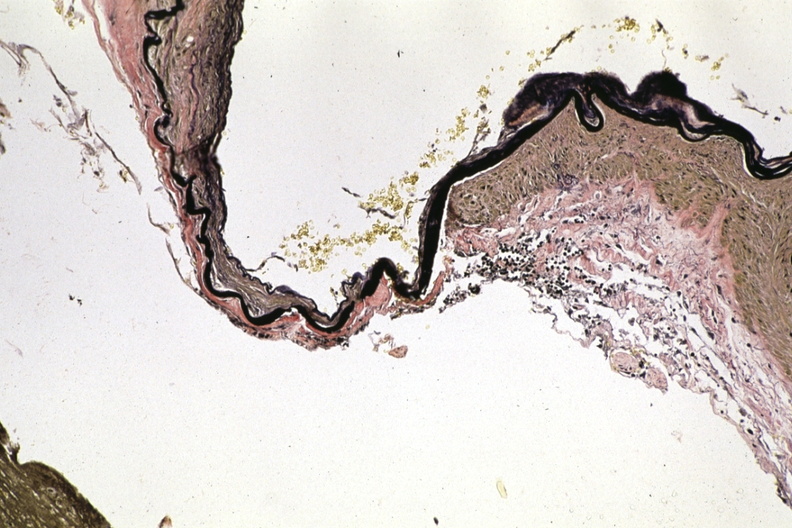

HISTOLOGY: CARDIOVASCULAR: VASCULATURE: Circle of Willis, nervous system: Berry Aneurysm: Micro low mag VVG very good demonstration of absence of media in aneurysm with normal wall junction